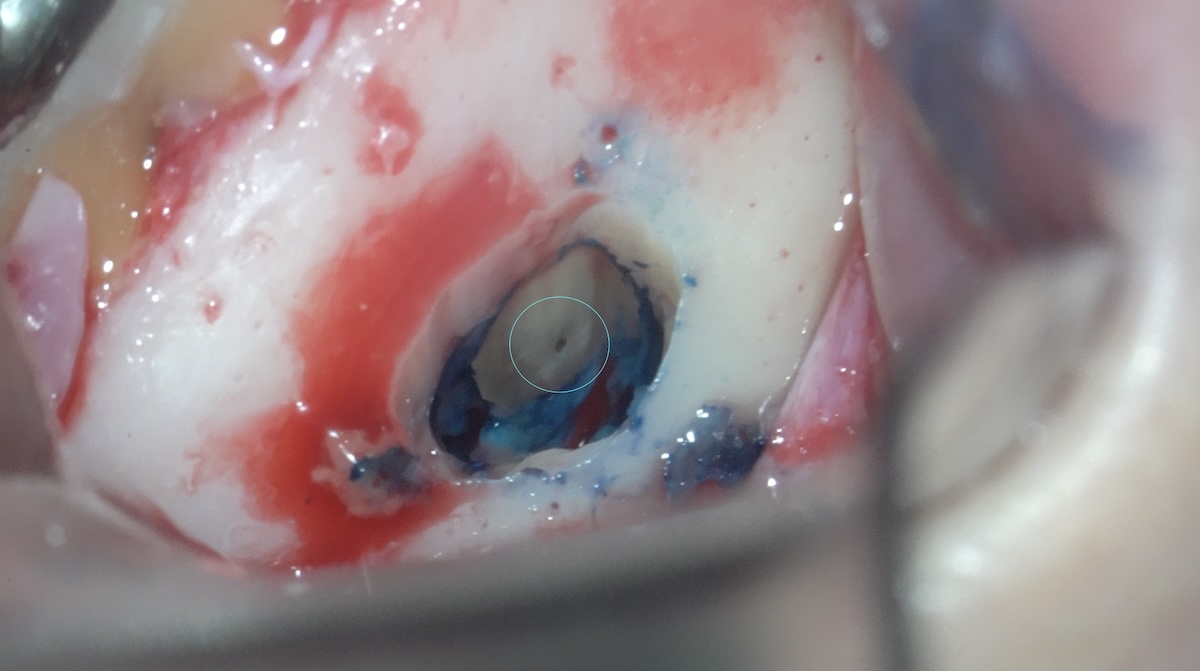

根尖を3m m切断。

中央部に根管が確認できる。

逆根管形成(🟰細菌の減少を図る)